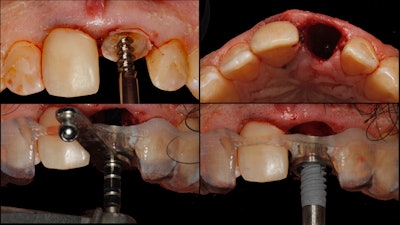

We determined that tooth #8 was restorable on caries excavation, so a full-contour composite buildup was done (the guide sleeve for #8 was removed from the surgical implant guide). Next, tooth #9 was extracted atraumatically.

Then we used a prefabricated surgical guide to direct the osteotomy drill sequence, immediately placing the NobelActive implant fixture (Nobel Biocare) in a fully guided fashion (figure 3).